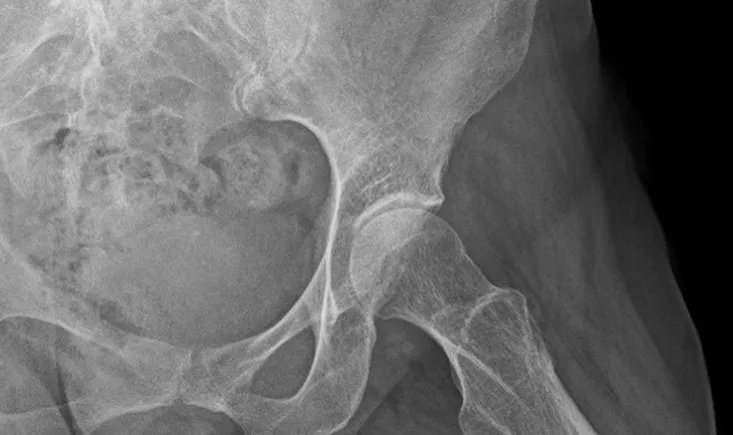

A 24-year-old female patient presents with hip pain. Pre-op X-rays reveal total lysis of the shelf: What cause…

This case discusses the causes of a hip pain, the different therapeutic options, and exposes the posterior min…